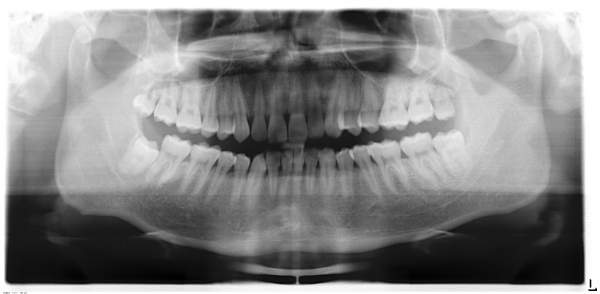

这是我牙齿的X-Ray 图。 我数着自己长了35颗牙齿,第36颗正在长。但听说一般人顶多只有32颗牙齿,怎么回事? 另外,我已经听医生的建议拔了左下颚的尽头牙,复查时医生建议我拔右上颚的最后一颗。 记得第一次看牙医的时候听说可能要拔四颗。烦的很。恳求牙医大神们帮我看看。 牙齿.jpg |